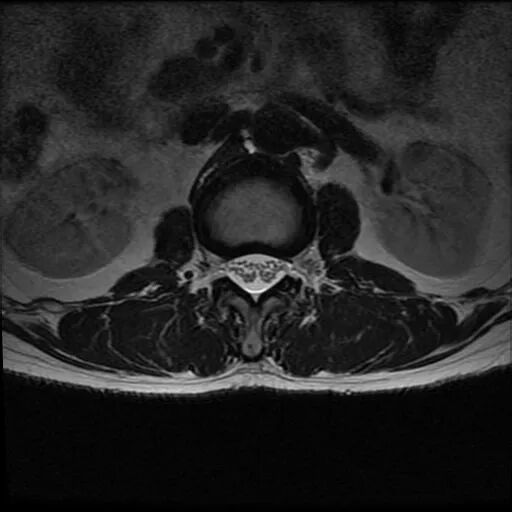

術(shù)前影像資料

圖2:術(shù)前MRI

?